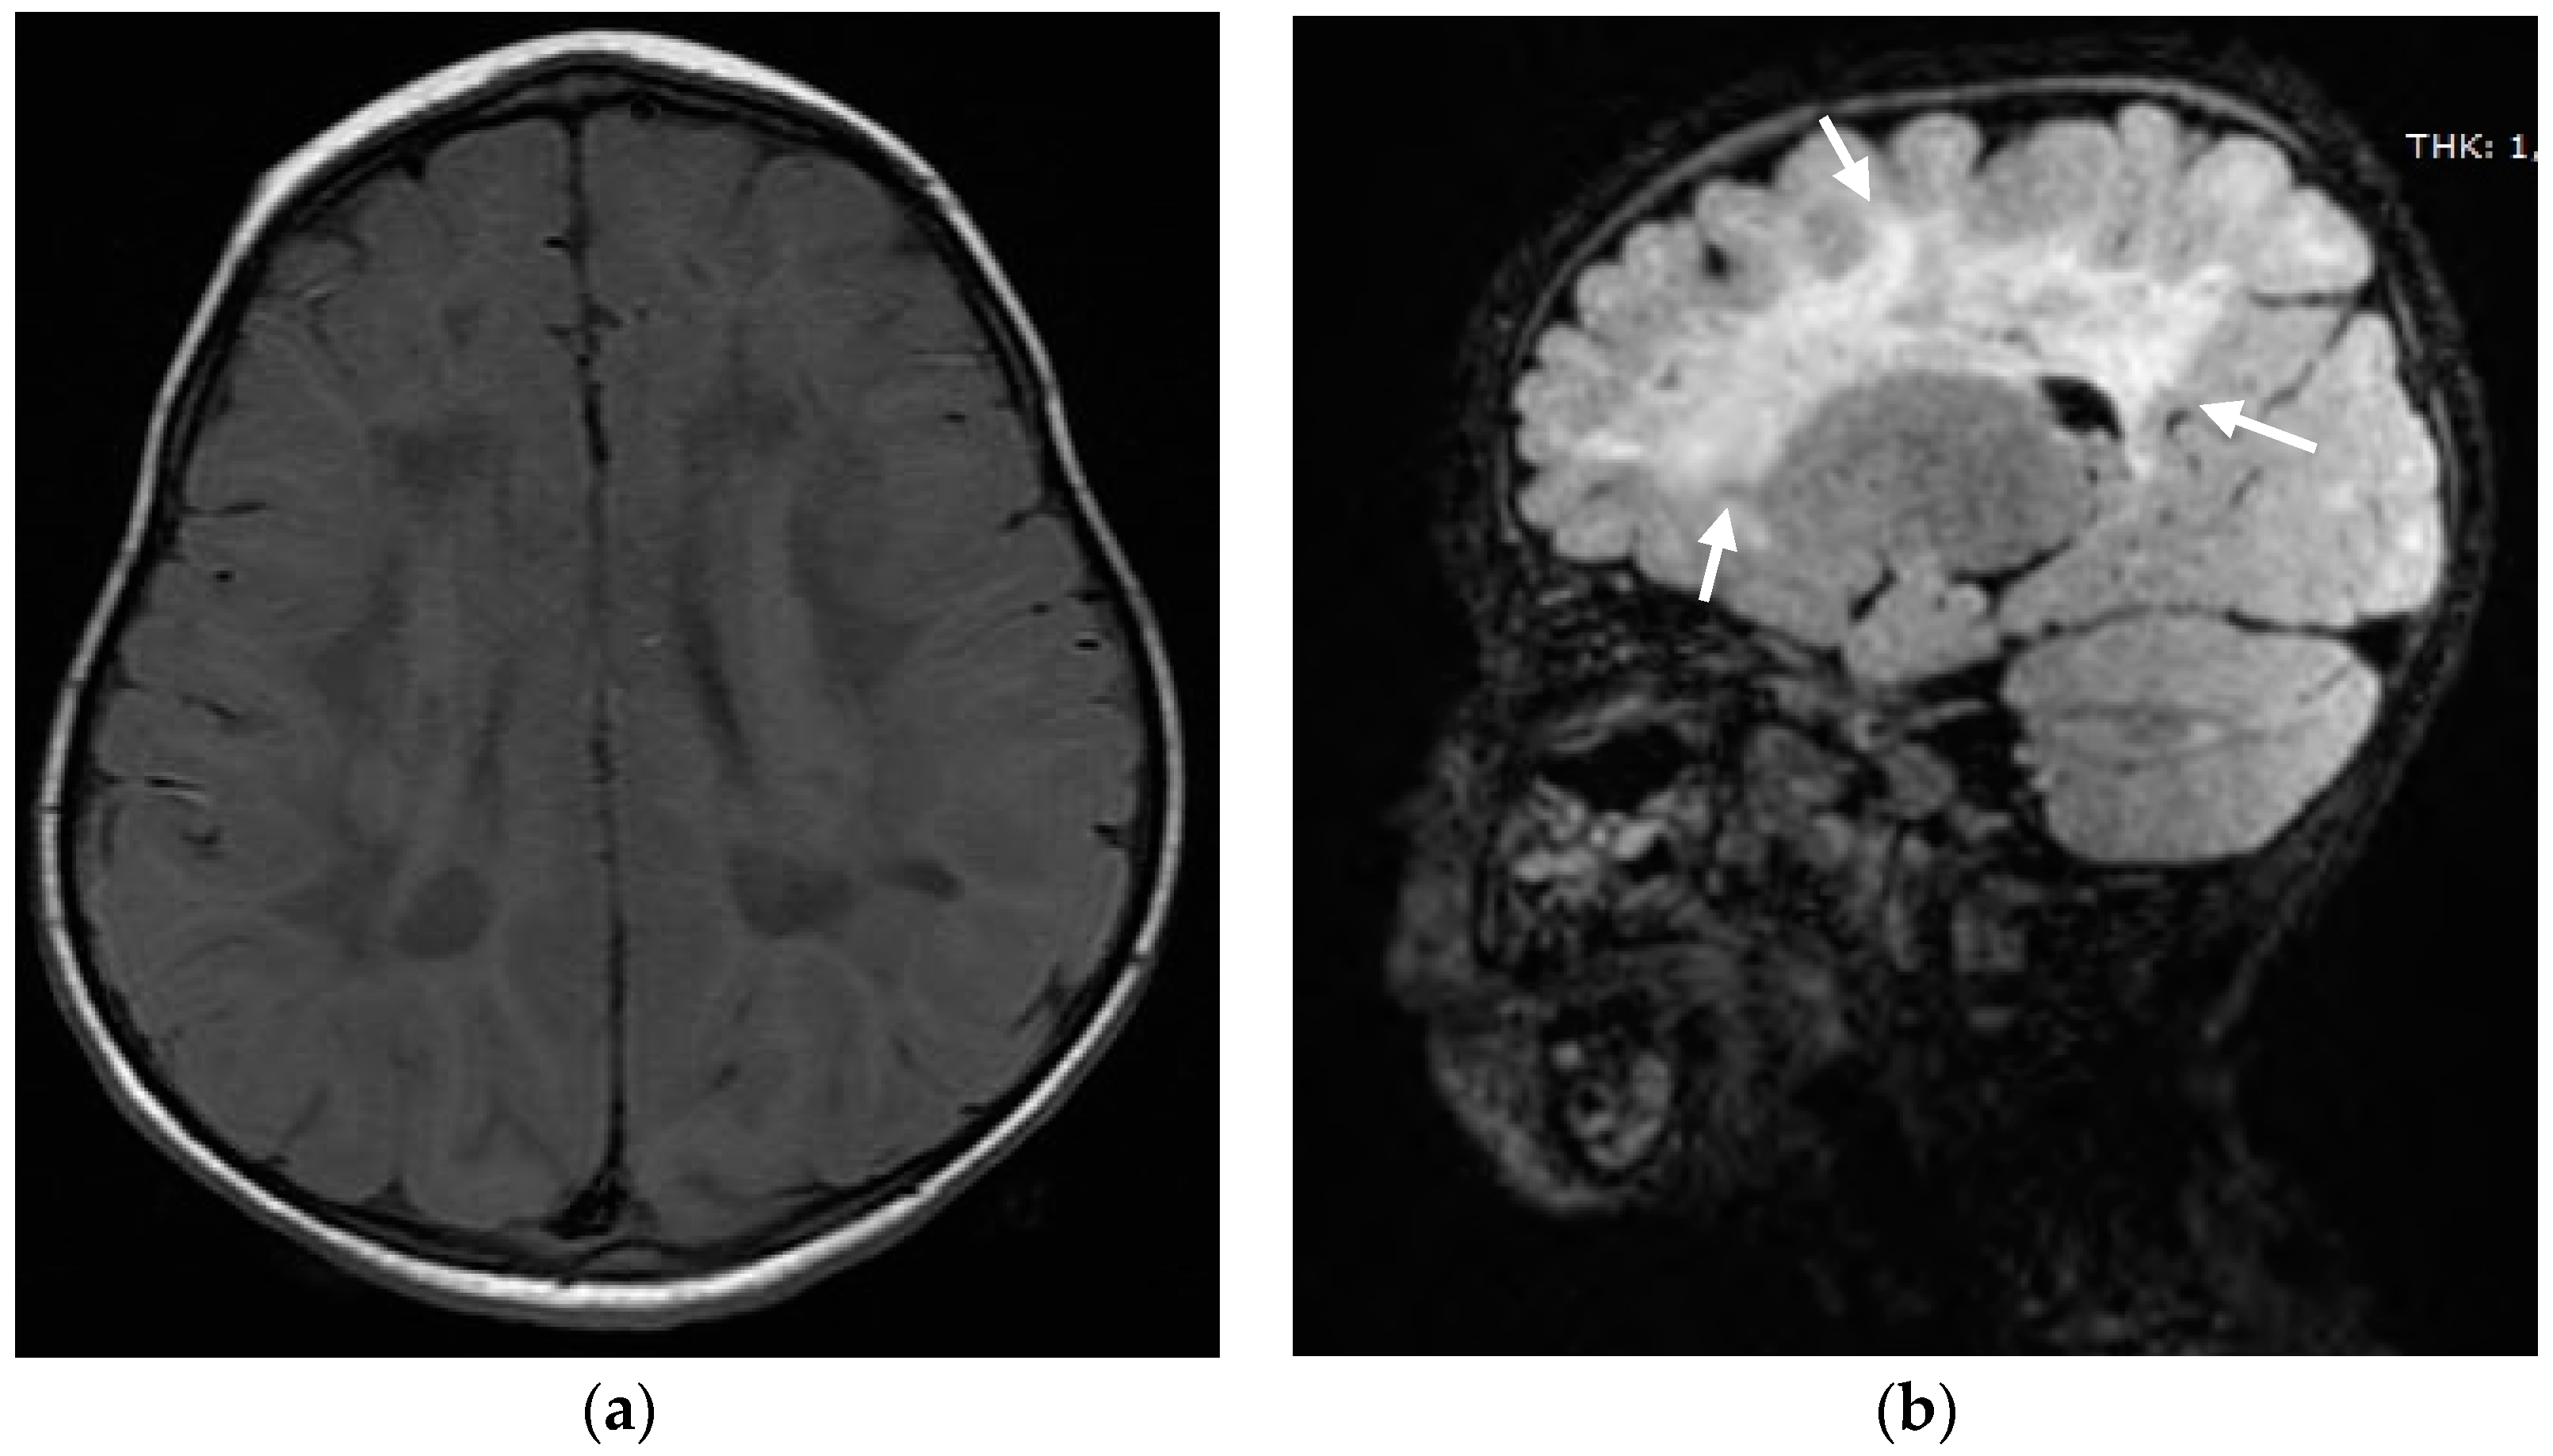

2. Case Report